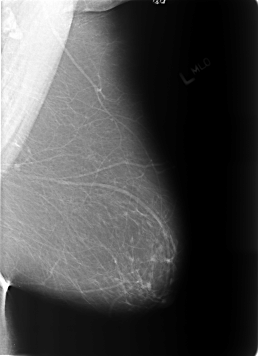

B_3172_1.LEFT_MLO

LEFT_MLO LINES 5696 PIXELS_PER_LINE 4128 BITS_PER_PIXEL 12 RESOLUTION 50 NON_OVERLAY

FILE: B_3172_1.RIGHT_MLO.OVERLAY

TOTAL_ABNORMALITIES 3

ABNORMALITY 1

LESION_TYPE MASS SHAPE LOBULATED-LYMPH_NODE MARGINS CIRCUMSCRIBED

ASSESSMENT 2

SUBTLETY 4

PATHOLOGY BENIGN_WITHOUT_CALLBACK

TOTAL_OUTLINES 1

BOUNDARY

ABNORMALITY 2

ABNORMALITY 3